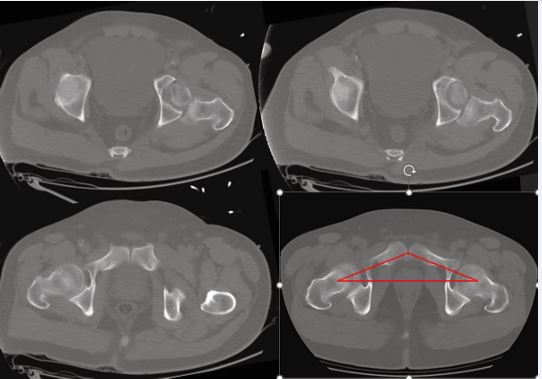

Proceed to EDF within ~24–36 h when oxygenation is adequate on lung-protective ventilation, vasopressor needs are stable or decreasing, acidosis/coagulopathy are corrected, and intracranial pressures are acceptable. Otherwise favor damage-control fixation with staged conversion. Because TBI biology may accelerate callus consolidation, timely anatomic reduction and fixation are advantageous once criteria are met; plan HO prophylaxis and neurosurgically aligned VTE prevention in parallel (Figure 7).

https://www.jscimedcentral.com/public/assets/images/uploads/image-1766059026-1.JPG

Figure 7 Axial pelvic CT for pre-operative planning Axial reconstructions across the hip joint; bottom-right panel includes a red overlay illustrating the acetabular roof contour/orientation used for planning.